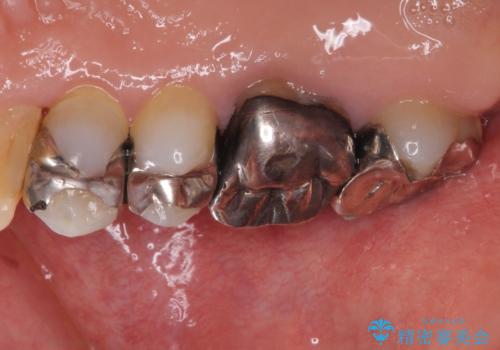

- 右上の小臼歯部に咬んだときに強い痛みを感じるとのことで来院された患者様です。

診査を行った結果、根管治療を行った後にオールセラミッククラウンにて補綴する治療計画となりました。

咬んだときの痛みに加えて夜間のズキズキする痛みもありましたが、1回目の根管治療実施後間もなく咬んだときの痛みがなくなったので、2回目に根管充填を行いました。